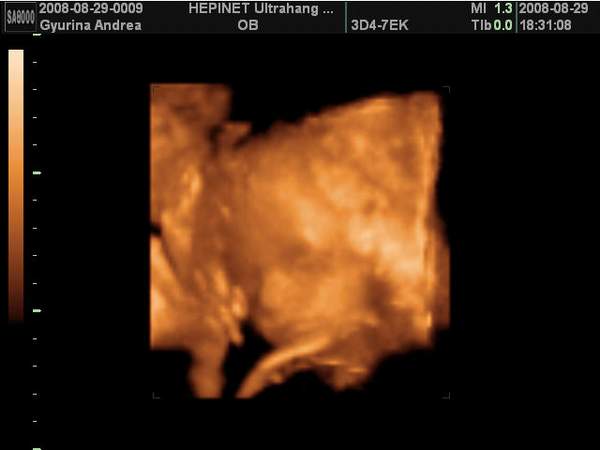

Én pénteken voltam 4D UH-on és végre megláttam a picurkám pofiját, ami szakasztott olyam, mint a nagyfiamé volt pinduri korában. Hát igen, van egy "nagy" fiam és lesz egy "kis"fiam is. Egyáltalán nem bánom, hogy fiú lett, majd a harmadik tuti lány lesz... :D

Dobok róla néhány képet, ha nem baj.

Kép Térd szaglászás...

Kép Nagyon töri valamin a buksiját...

Kép